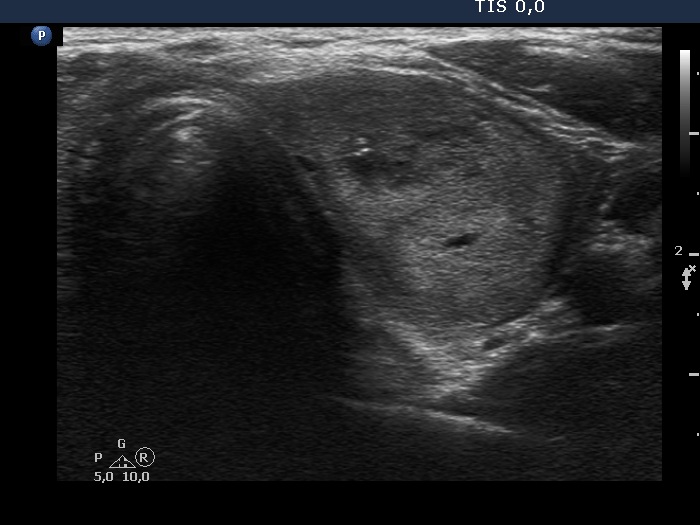

Ultrasonography. The thyroid was echonormal. There were two nodules in the left lobe. The upper, minimally-moderately hypoechoic showed taller-than-wide sign and had two microcalcifications. The lower nodule was a dominantly echonormal lesion. This showed an incomplete halo and signs of perinodular blood flow. The volume of the nodules has not been changed since their recognition.